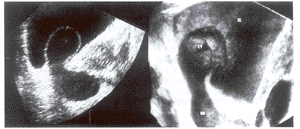

摘 要 目的:评估三维超声、彩色多普勒超声对输尿管囊肿的应用价值。方法:用三维、彩色多普勒血流观察了10例输尿管囊肿的立体形态及喷尿情况。结果:三维超声立体感强,形态逼真,定位准确。彩色多普勒显像示喷尿的尿流束由囊肿内向膀胱喷射时较为明显,表现为细而色艳的彩色流束,而由输尿管向囊肿内喷射时流束则呈粗而色暗。结论:三维超声和彩色多普勒超声能提高诊断输尿管囊肿的准确率,为临床提供更准确的诊疗信息。